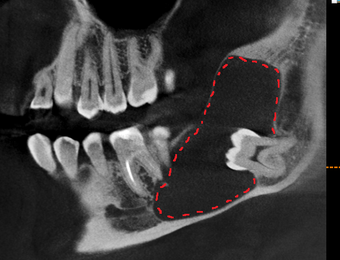

Красным пунктиром я выделил границы этой кисты на срезах компьютерной томографии. Зуб, как вы можете заметить, находится аж у угла челюсти. Если говорить простым языком, то зуб сместился ввиду давления, которое формируется внутри кисты, за счёт чего, кстати, она и увеличивается. Киста достаточно большая, в связи с чем корни 6-го и 7-го зуба были вовлечены в воспалительный процесс. Если сравнить расположение 8-ки с противоположной стороны, то можно заметить, что она располагается намного ближе к 7-му зубу.

Что мы видим? Темное пятно в области проведенной операции сохраняется, что нормально, потому как прошел всего месяц с момента удаления. Заживление проходит хорошо, каких-либо проблем в восстановлении не наблюдается. Не зря я отметил пунктиром область зуба мудрости с противоположной стороны, потому как там есть точно такая же фолликулярная киста, как и слева, но на начальных этапах своего роста.

Красными стрелками я отметил постепенное «появление» периодонтальной щели. Вон та черная полоска (пространство) между корнем зуба и костной тканью. Грубо говоря, там связка, которая выполняет опорно-удерживающую функцию, что позволяет зубу несколько амортизировать при жевании.

На данном снимке видно, что область удаления продолжает восстанавливаться, всё четче видны очертания нижнечелюстного канала, в котором проходит одноименный нерв.